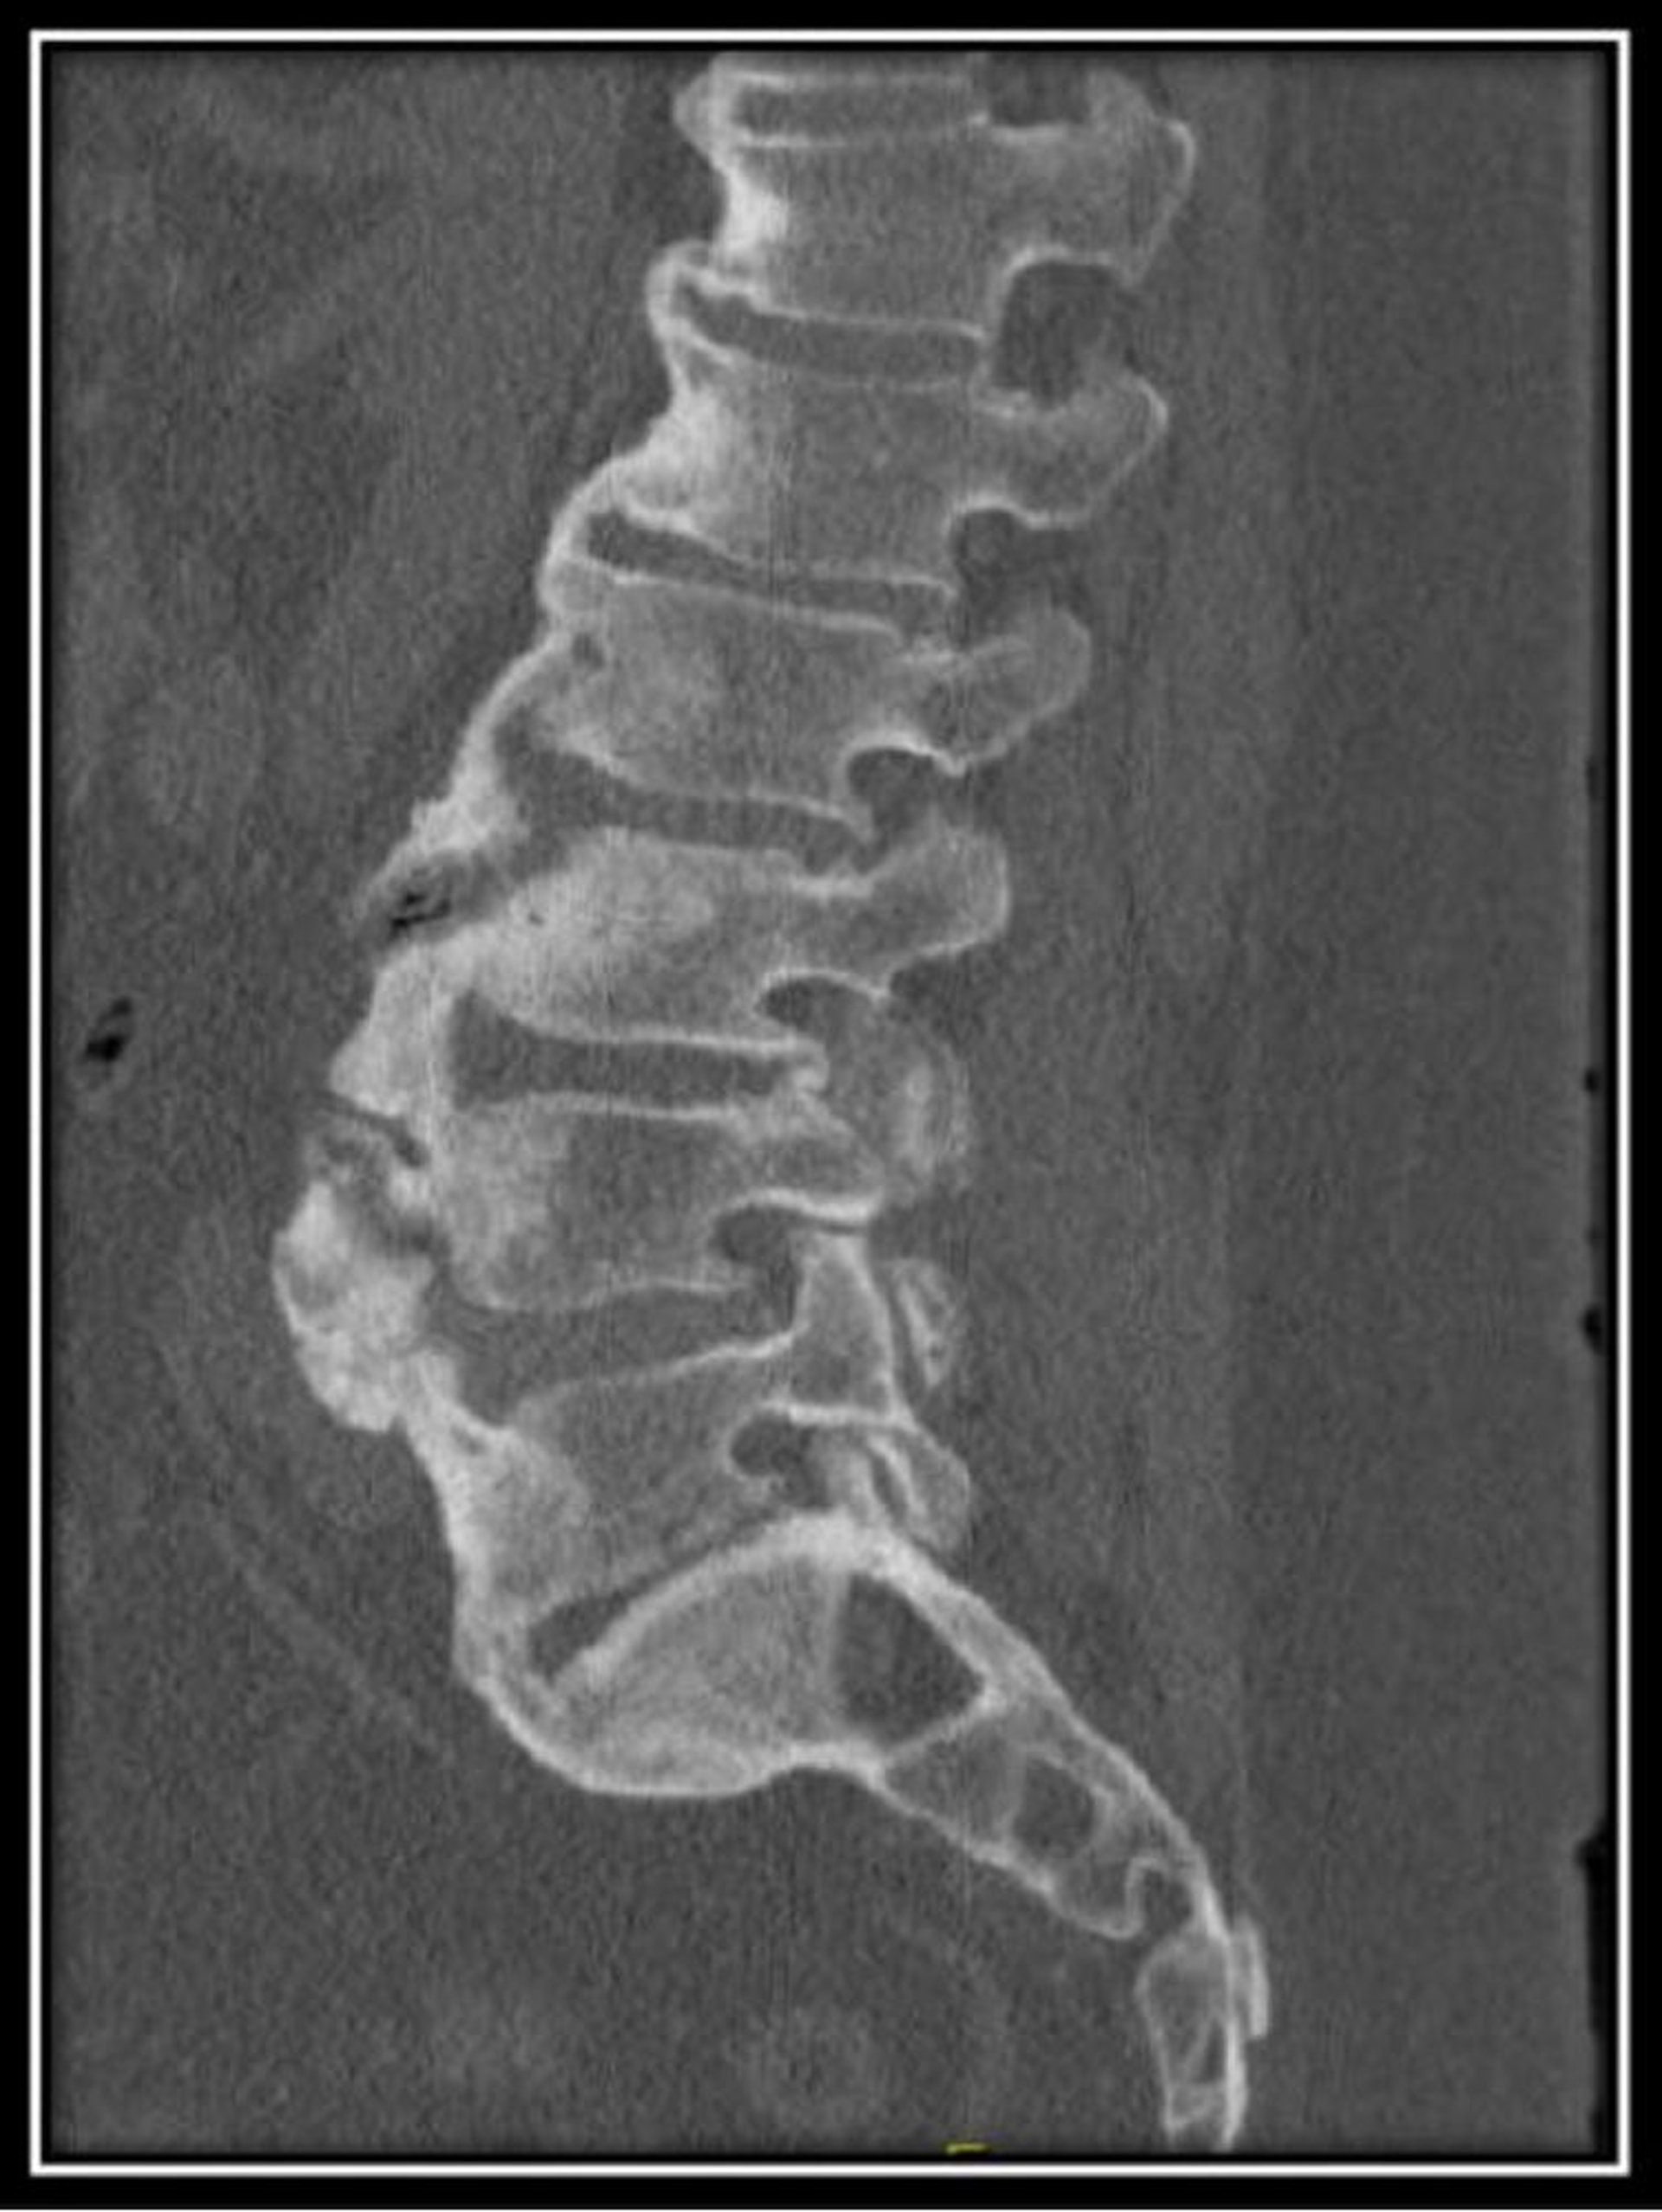

Hyperostose squelettique idiopathique diffuse (TDM)

Cette TDM du rachis lombaire chez un patient présentant une hyperostose squelettique idiopathique diffuse montre des hauteurs normales des corps vertébraux avec des ostéophytes antérieurs diffus avec des espaces discaux maintenus.

Image courtoisie de Kinanah Yaseen, MD.